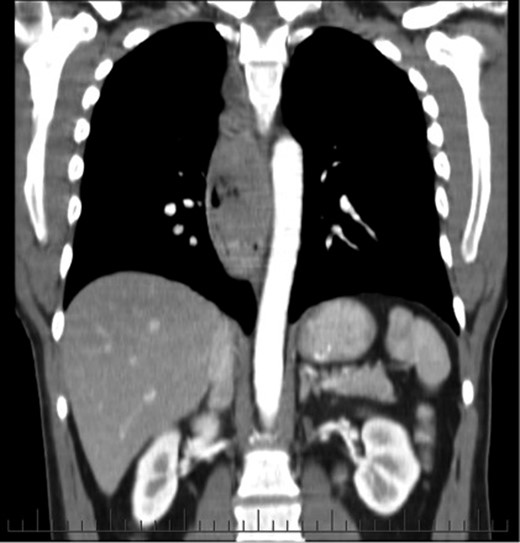

His initial endoscopy showed a 12 cm fungating, pigmented tumour occupying most of lower oesophageal lumen (Fig. 1). The biopsy was highly suggestive of primary malignant melanoma. Staging computed tomography (CT) and positron emission tomography (PET) showed extensive mediastinal, left supraclavicular and coeliac lymph node enlargement (FDG avid) with no evidence of metastatic disease (Fig. 2).

He was commenced on palliative radiotherapy with good symptomatic improvement. However, serial CT imaging showed interval development of metastatic lesions within the pericardial tissues, chest and liver. New metastatic nodules within the oesophagus and stomach were seen on repeat endoscopy. He was worked up for chemotherapy, however, succumbed to respiratory failure and passed away shortly before initiation of therapy.